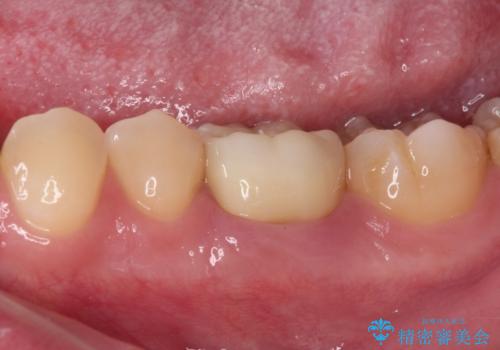

仮歯は見た目は白くても、粘着性の食事がこびりついたり、舌感がざらついていたりと、不快感を感じるだけでなく、長期装着するとむし歯が進行するリスクが高まります。

フルジルコニアクラウンを装着したことにより、舌感が改善されるとともに、むし歯再発リスクを軽減することができました。